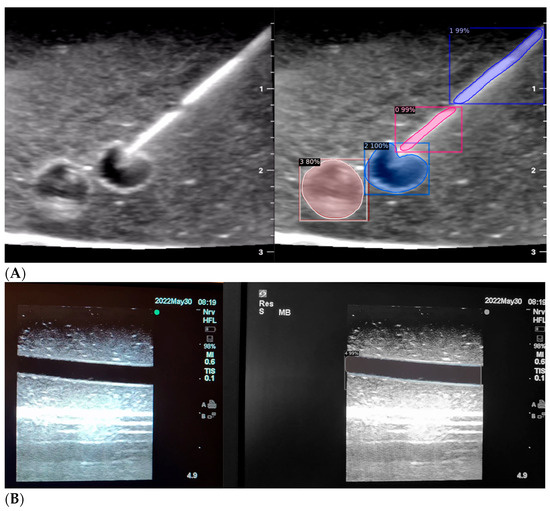

When the model is applied, the original ultrasound image is overlaid with a new layer that presents the detection results, offering insights into predicted target areas (Figure 4 and Figure 5).

The segmentation area represents the region identified by the model as each object class (needle tip, needle body, blood vessel, or nerve bundle). This area is visually highlighted, allowing for a clear understanding of what structure is of interest. To provide additional context, a bounding box in the shape of a square is placed around the segmentation area, enclosing the detected object and providing a concise representation of its location. These are illustrated in Figure 4, Figure 5 and Figure 6, with original images on the left and overlayed images on the right for our three different phantom models.

In order to assess the confidence level of the model’s predictions, a confidence percentage is assigned for each object class labelled (Figure 4, Figure 5 and Figure 6). This percentage represents the probability of a true positive detection by the model. It quantifies the model’s level of certainty regarding the accuracy of its prediction for each detected defect.

Figure 4. Model inference in Phantom A (Agar 2.5% with septanol and psyllium husk).